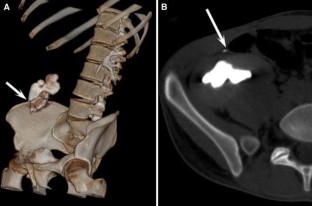

Usefulness of computed tomography performed immediately after excretory urography in patients with delayed opacification or dilated upper urinary tract of unknown cause

To evaluate the diagnostic value of computed tomography (CT) performed immediately after excretory urography (EU) in patients with delayed renal opacification or dilated upper urinary system with nonconclusive diagnosis after EU.

CT was performed immediately after EU in 39 patients with delayed opacification or dilated upper urinary system of unknown cause, without additional intravenous contrast administration for the CT study. We classified EU + CT findings as benign or malignant causes and we compared our results with the final diagnosis.

The combination of EU + CT correctly diagnosed 38 out of the 39 cases with a sensitivity of 97%. Correct diagnosis was established in all malignant cases (n = 17) but one benign case consistent with blood clots in the upper urinary tract was incorrectly diagnosed as a multicentric urothelial carcinoma. Sensitivity, specificity, and accuracy for the diagnosis of the underlying cause with EU + CT was 100%, 95%, and 97%, respectively. The final diagnoses were: urothelial carcinoma (n = 10), stone disease (n = 10), bladder tumor (n = 4), benign post-treatment ureteral stenosis (n = 4), ureteral invasion (n = 3), benign bladder disease (n = 2), urinary tract infections (n = 2), crossing vessels (n = 1), ureteropelvic junction obstruction (n = 1), retrocaval ureter (n = 1), and blood clots in the upper urinary tract due to bleeding renal metastasis from lung cancer (n = 1).

Combined EU and CT study allowed correct diagnosis of the underlying cause of delayed excretion or upper urinary tract dilatation in 97% of cases. The combination of EU and CT provides diagnosis reducing time and radiation.